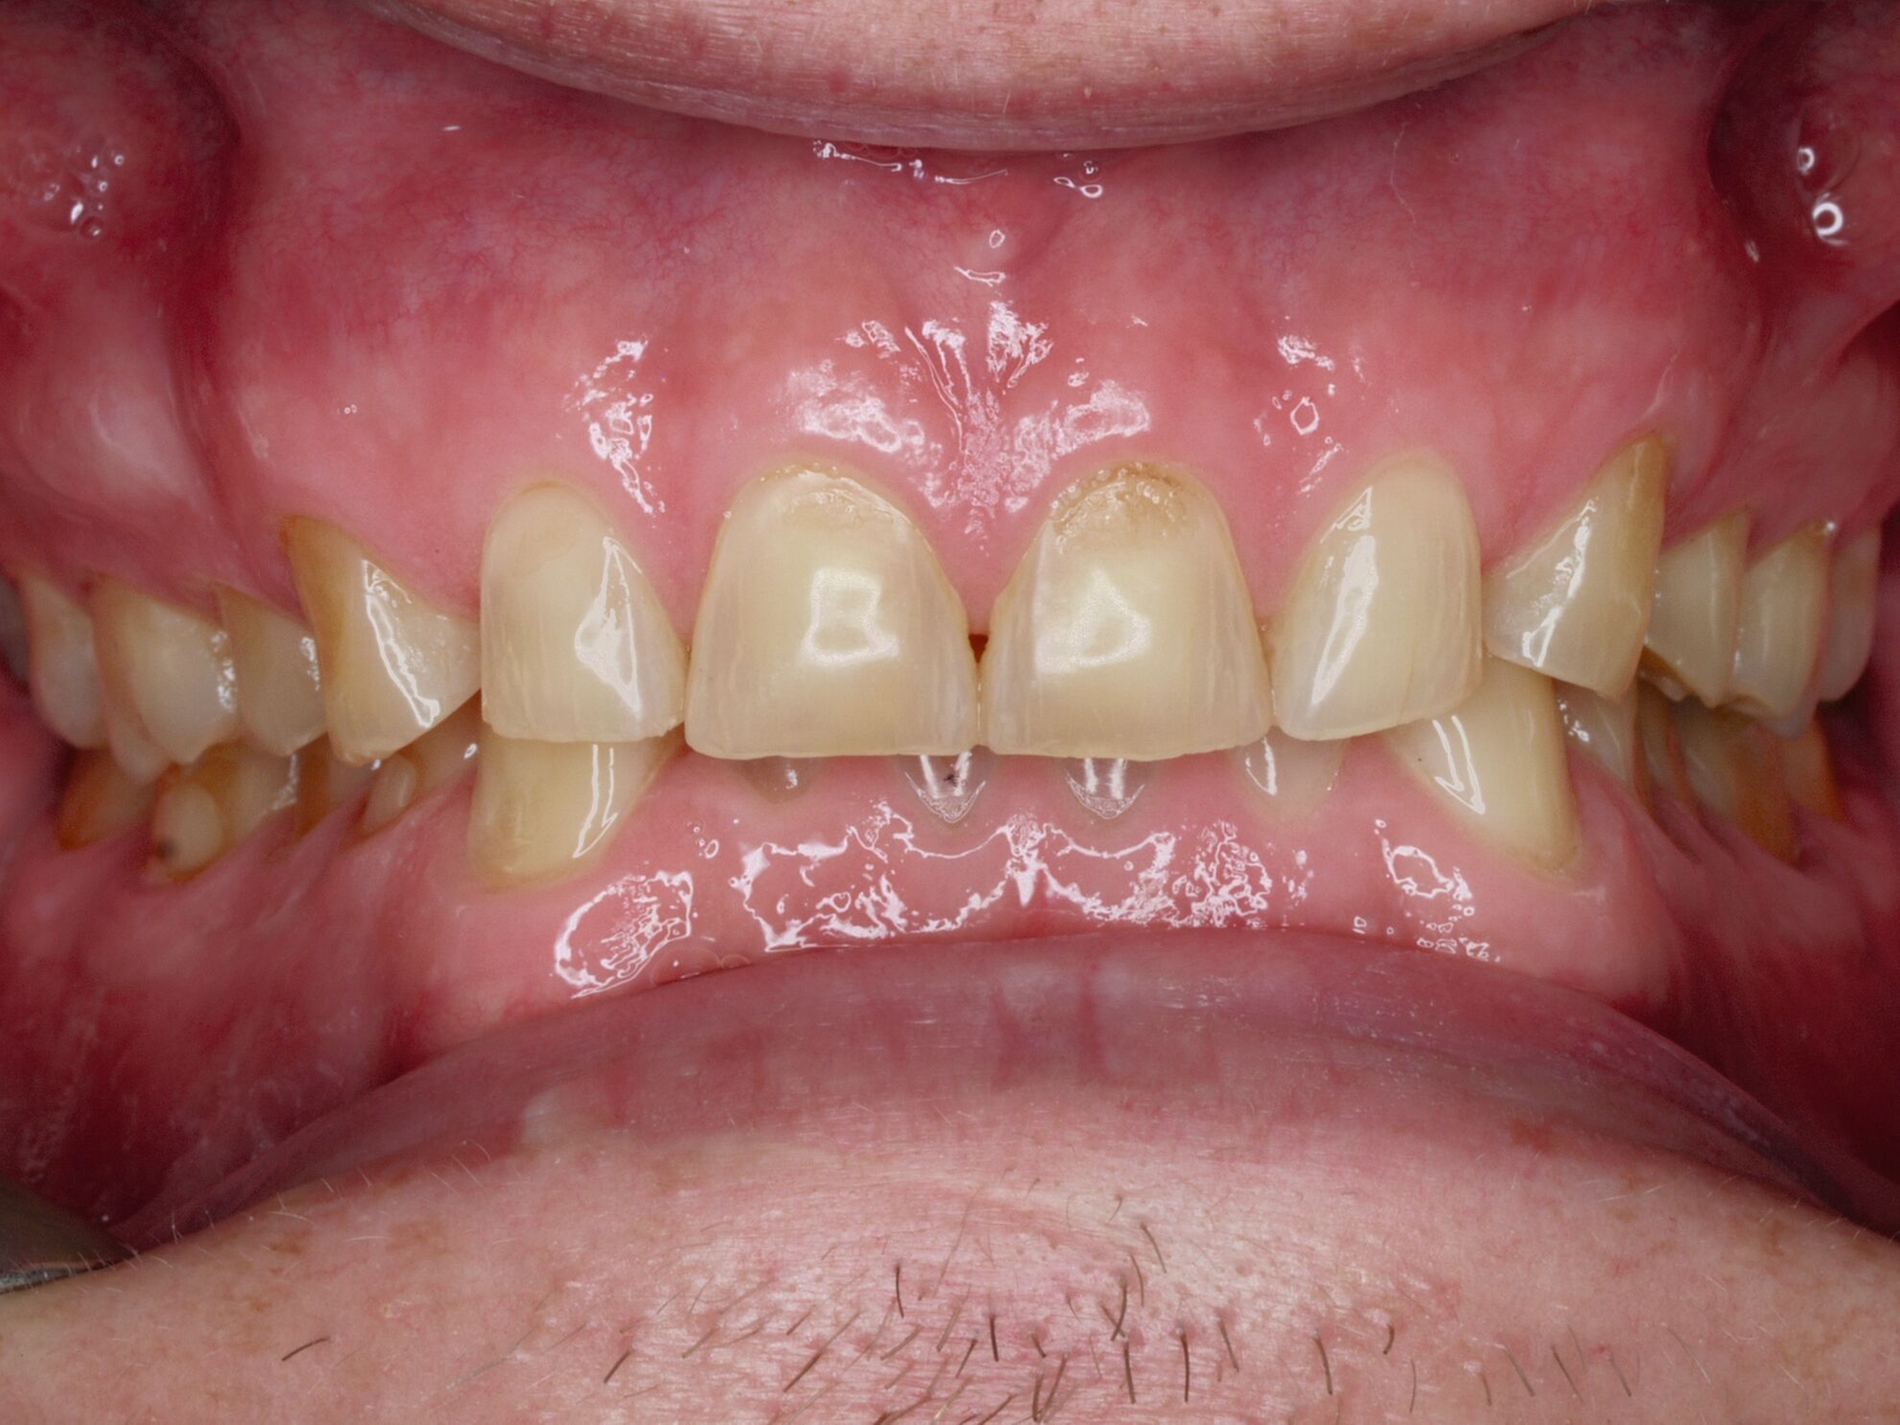

Das unter Beteiligung des Autors entwickelte Tooth Wear Evaluation System (TWES) 2.0 [Wetselaar et al., 2020] identifiziert per Screening Patienten mit erhöhten Verschleißwerten, vergleichbar mit dem PSI in der Parodontologie oder dem CMD-Kurzbefund. Bei auffälligen Werten folgt ein differenzierter Zahnverschleiß-Status einschließlich der Erfassung oraler und vestibulärer Substanzverluste [Wetselaar et al., 2016 sowie von Pathologie-Symptomen und einer strukturierten Diagnose [Tonetti und Sanz, 2019; Wetselaar, 2020]. Den Einsatz in der Praxis illustriert der in den Abbildungen beschriebene Patientenfall aus dem CMD-Centrum Hamburg-Eppendorf.

Zahnverschleiß-Status

Im Unterschied zum Zahnverschleiß-Screening wertet der Zahnverschleiß-Status den höchsten Verschleißgrad pro Zahn aus, und zwar okklusal/inzisal, oral und vestibulär (Abbildungen 4b und 4c, Tabelle 1). Wichtig für die Planung therapeutischer Maßnahmen ist die Frage, welche Zähne okklusal in Kontakt stehen, denn die Behandlung von Zähnen mit erheblichem Zahnverschleiß lässt keinen weiteren Substanzverlust zu und erfordert bei Zähnen in Kontakt absehbar eine Erhöhung der vertikalen Dimension der Okklusion.

Der Zahnverschleiß-Status erfasst auch zehn Kriterien, die nach der Literatur Anzeichen eines pathologischen Geschehens sind. Als pathologisch wird Zahnverschleiß demnach eingeordnet, wenn bei Grad 3 zusätzlich mindestens ein Pathologie-Kriterium vorliegt (Abbildung 6).

Ergänzt wird der Zahnverschleiß-Status durch 20 Merkmale, die jeweils chemischen und mechanischen Ursachen zugeordnet sind und in der summativen Auswertung zeigen, welche Ursachen offensichtlich dem Geschehen zugrunde liegen. Dies ist auch bei vermeintlich eindeutigen Fällen hilfreich, da zuweilen mehrere Faktoren ineinandergreifen, die dann möglichst alle abzustellen sind, bei erheblichem oder extremem pathologischem Zahnverschleiß einhergehend mit einer eventuellen restaurativen Therapie.

Wichtig für das Therapiekonzept ist zudem der Umfang des Zahnverschleißes. Die Auswertung unterscheidet daher lokalisierten und generalisierten Zahnverschleiß.

Im Beispiel ist daher die Diagnose ein generalisierter erheblicher und lokalisierter moderater pathologischer Zahnverschleiß überwiegend mechanischer und zudem chemischer Ursache. Die sich daraus ableitende Erkenntnis ist, dass in allen Sextanten Zähne freiliegende Dentinkerne aufweisen (generalisierter moderater Zahnverschleiß), dass darüber hinaus Zähne erheblich geschädigt und somit gefährdet sind, dass Merkmale eines pathologischen Geschehens bestehen – und dass als Ursache neben dem dominierenden Bruxismus ein Säureeinfluss hinzukommt.

Auch wenn Restaurationen nach Möglichkeit vermieden werden sollten, ist deren Verfügbarkeit für die Betroffenen individuell höchst wichtig, weil sie bestehende Schmerzen beseitigt, die verlorengegangene Kauleistung wiederherstellt und ästhetische und nicht zuletzt auch phonetische Einschränkungen aufhebt. Bei dem in den Abbildungen beschriebenen Fall korrelierte der erhebliche Zahnverschleiß mit der Lokalisation der Zahnschmerzen des Patienten. Direkte Restaurationen mit Kompositen hatten keinen Bestand. Die durchgeführte restaurative Behandlung hingegen hat Bestand, die Schmerzen waren danach umgehend verschwunden und sind seit zehn Jahren nicht wiedergekehrt.